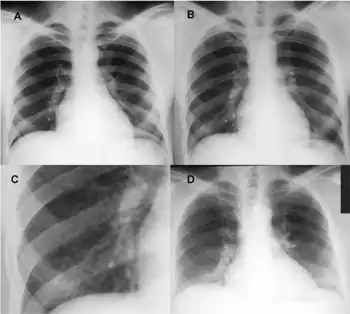

- Chest X-ray